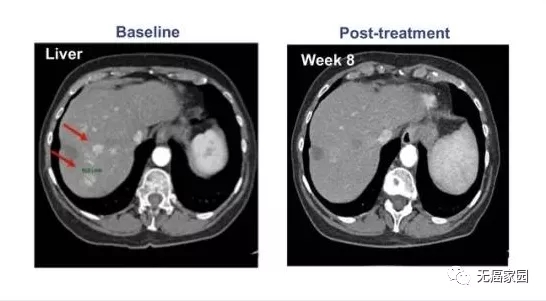

参与的9例患者均接受过手术及常规放化疗,但出现失败或不耐受的现象。在接受最高剂量治疗的4例患者中,有1例患者获得完全缓解,CT扫描显示,患者体内所有病变都消失了,而且完全缓解后已持续半年以上无任何复发的状态!

其他患者(队列1、队列2)最佳反应是病情稳定。队列2中的1例患者在治疗1个月后原发病灶体积未缩小,但纵膈淋巴结转移灶体积明显缩小!